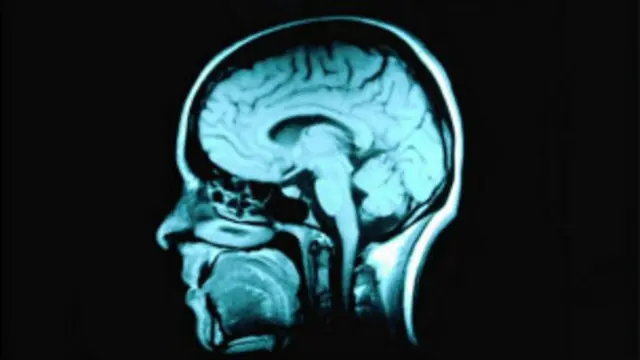

Метод, названный "функциональной магнитно-резонансной томографией", открыл новые перспективы - оказалось возможно через отслеживание кровотока мозга идентифицировать конкретные слова или понятия, о которых в этот момент думает человек.

Исследователи сосредоточили внимание на одном участке мозга - верхней височной извилине.

Эта часть слуховой системы - один из самых высокоорганизованных участков мозга, ответственный за то, что мы извлекаем из потока звуков некий смысл, различаем слова и понимаем их лингвистическое значение.

При помощи компьютерной модели была составлена "карта" с указанием, какие участки мозга и с какой интенсивностью посылают импульсы, когда ухо слышит звуки на различных частотах.